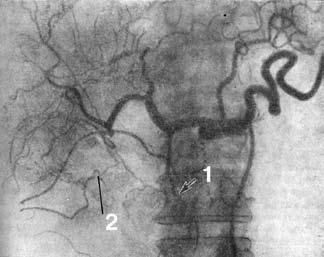

Ангиография (АГ). При РПЖ возникают изменения в ее сосудах или сосудах, расположенных в непосредственной близости к железе: изменяется просвет и положение сосудов, нарушается кровоток, появляются атипичные сосуды. Существует несколько методик контрастирования артерий и вен ПЖ: 1) спленопортография, 2) чрескожная чреспеченочная портогепатография, 3) целиакография. Для опухоли характерны смещение, деформация, окклюзия сосудов. Диагностическая точность метода составляет около 70 % (рис. 109).

Рис. 109. Целиакограмма: рак головки поджелудочной железы.

Артериальная фаза. Ампутация желудочно-двенадцатиперстной артерии (1), обеднение сосудистого рисунка в зоне опухоли (2).